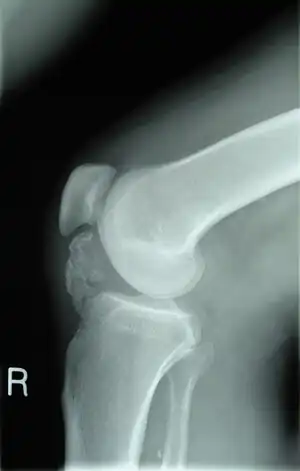

| X-ray knee (side view): ossification in the peritendinous tissues in a person with osteochondroma. | |